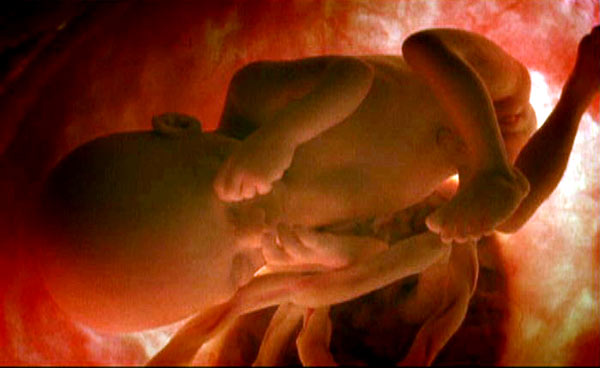

He recuperado la galería de fotos de en el vientre materno de mi vieja web. Como os dije en el artículo anterior, estoy en el momento oportuno para ver con detalle estas fotografías sobre la gestación. Podeis descargar las fotos aquí o ver la galería a continuación

También podeis ver la galería con comentarios a pie de cada fotografía en el diario 20minutos

Adicionalmente y aunque no sean las de National Geographic teneis otra galería de fotos sobre la gestación titulada La Vida en el Vientre Materno

Por cierto, que flipe la antepenúltima foto. Se le ve toda la carita perfectamente ¿Vosotros os hicisteis la 3D? Tiene que ser impresionante ver la cara de tu bebé antes de que nazca

El Video de National G.que comentas me lo prestó Bixo y la verdad es que es digno de ver ya que te va explicando semana a semana como crece el bixito y cómo te vas sintiendo tú como mujer y los cambios que tienes en tu cuerpo,es una pasada.